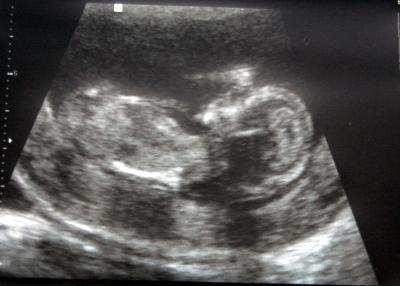

Schaut mal ich habe auch ein Bildchen bekommen.... Man sieht Köpfchen und Brust und die Maus hält ihre Hand vor das Gesicht.... LG Steffi

Bild zu Das Bild von der NFM-Messung - Forum für Mai - Mamis

11cm im Ganzen ;-) also nicht SSL....